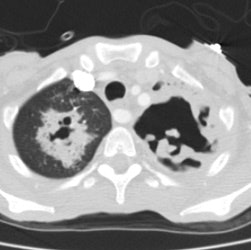

Extensive tuberculosis:

The patient below presented for evaluation of an abnormal CXR. The CT revealed bilateral extensive cavitary consolidations (essentially replacing the left lung), a large cavitary lesion in the right apex, and multiple scattered nodules and "tree-in-bud" opacities. The patient was found to have active TB.